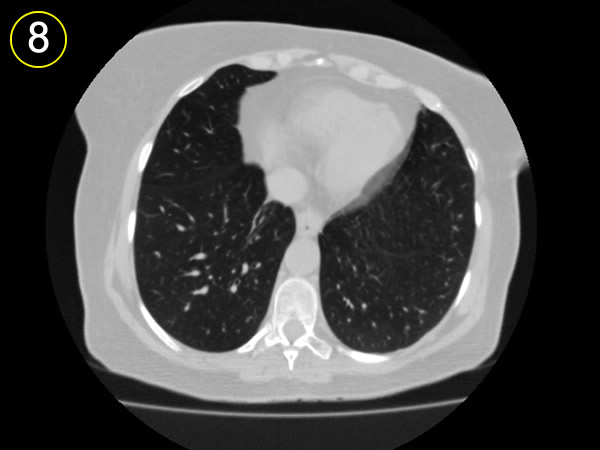

La tomografía

computarizada del tórax

y su adecuada interpretación es de gran ayuda diagnóstica

en las patologias del tórax.